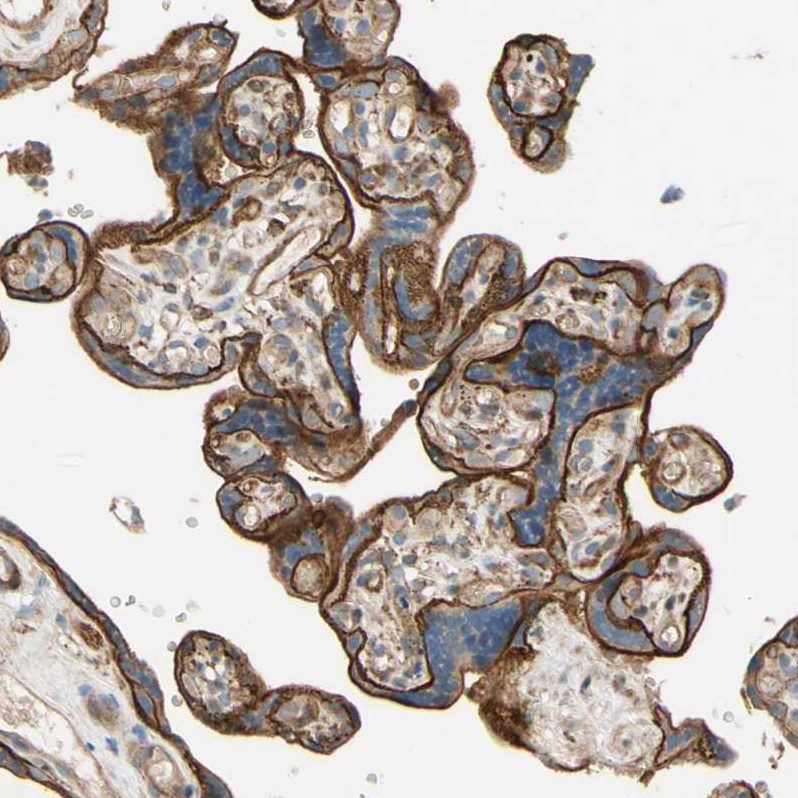

Immunohistochemical staining of human heart muscle shows moderate cytoplasmic positivity in cardiomyocytes.